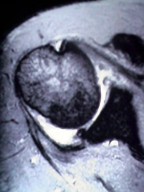

Axial MRI shows joint fluid [white] on the left, with labral degeneration. Coronal MRI image on the right shows edema of the supraspinatus tendon resulting from an impinging distal acromial spur.